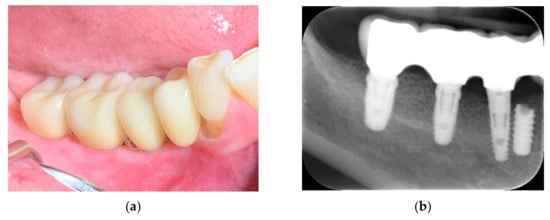

The 66-year-old patient was a healthy non-smoking female patient who lost her right mandibular molars for a long time. Previous implant placement was not successful, and an implant failure was present due to an implant fracture. Due to the risk of damaging the mandibular nerve, the broken implant was left in the jaw (as a “sleeping” implant), covered completely by the bone. That implant was left in the jaw, which presented a severe atrophy, with a remaining residual bone height of approximately 4 mm. Based on the height, the placement of short implants was not an option, and the patient was informed about the different grafting options, as well as the possible intraoperative and postoperative complications (Figure 1).

Figure 1.

Clinical situation: bone deficiency in the right posterior mandible.

After 15 months, the patient returned to the practice for a regular check-up. The soft tissues presented a healthy condition and pink color (Figure 21a), with excellent plaque control. The postoperative radiograph showed bone remodeling at the distal side of tooth #30 (Figure 21b).

Figure 21.

Follow-up at 15 months: clinical view (a) and control radiograph (b).